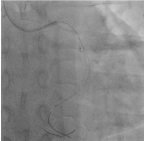

As the first attempt, we used TREK balloon 2.5 × 15 mm anchored in the second run through wire placed in left anterior descending artery (Figure 7) and tried to extract the broken tip. Failed to retrieve with the anchoring balloon technique. The second run through wire was advanced across the LCx and positioned in the distal LCx, twisting parallel wire technique was tried (Figure 8). The broken tip was moving along with the guide wire freely from proximal to distal LCx but failed to pass from the very proximal and ostial LCx. Planned to engulf by using guide catheter extension, Guidezilla (Boston Scientific, USA) has not even failed but resulting in dislodgement further down to distal LCx (Figure 9). Further attempt to trap with low profile TREK 3.0 × 15 mm by positioning beyond the tip, inflating upto 6 atm pressure (Figure 10) also not working well in retrieving the broken tip. By using various techniques including twisting parallel wire technique, using low profile balloon on another parallel guidewire, reaching out to the tip by using guide catheter extension, Guidezilla (Boston Scientific, USA) has failed and leaving the last option as catching with the snare. The first attempt to snare with 10mm × 120cm snare only dislodged the broken tip more distally. The second snare device 4mm × 200cm Goose Neck Amplatz Microsnare finally managed to capture the guidewire distal to the broken tip (Figure 11) and the whole system was retrieved successfully (Figure 12,13). POBA along LCx was done by using 3.0 × 15 mm and upsize to 5.0 × 15 mm balloon. Final angiogram revealed flow in the LCx was re-established (TIMI II flow) with no major dissection or perforation was identified (Figure 14). In view of established flow within the ectatic coronary and improving chest pain, we didn’t proceed with stenting. The patient was discharged uneventfully after completing 5 days of low molecular weight heparin and discharged with dual antiplatelet therapy, Aspirin and Plavix and non-vitamin K antagonist oral anticoagulant (NOAC). The patient was reviewed 3 months and 6 months duration, he was asymptomatic with echocardiogram showing left ventricular ejection fraction of 65% with no regional wall motion abnormality.

Figure 14. Final angiogram result